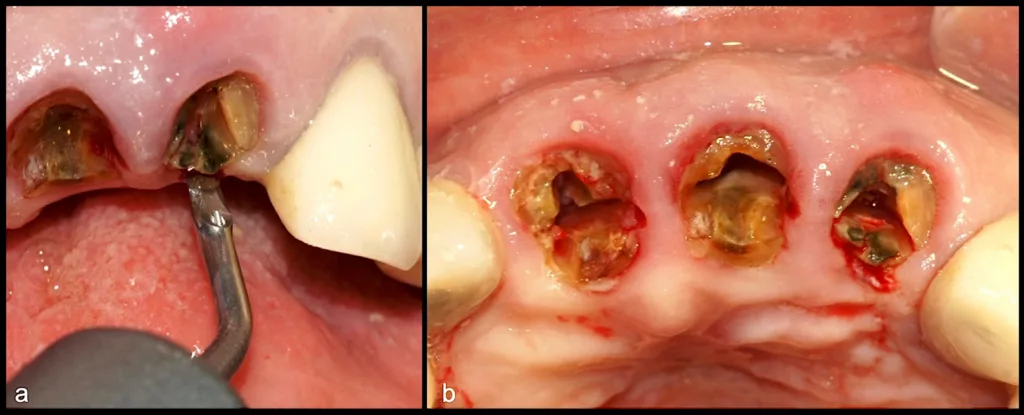

Dr. Rosas: Mit der atraumatischen Extraktion können wir Zähne entfernen, ohne die vestibuläre Knochenwand zu verletzen. Diese ist meist sehr dünn, oft weniger als 0,5 Millimeter, und deshalb besonders anfällig. Gleichzeitig bleibt auch der proximale Knochenkamm erhalten, was vor allem im Frontzahnbereich wichtig ist – dort entscheidet er über die Ästhetik der Zahnfleischpapillen. Bei einer Sofortimplantation hat das folgende Vorteile: Wir können die komplette Architektur von Hart- und Weichgewebe bewahren, was den Implantaten ein viel natürlicheres Aussehen verleiht.

Für die Patienten bedeutet das: weniger Trauma beim Eingriff, mehr Komfort und postoperativ weniger Schmerzen und Schwellungen. Wenn wir es außerdem mit trockenen Alveolen zu tun haben, können spezielle Piezo-Instrumente helfen, die Alveolenwände sanft abzutragen. Durch dieses vorsichtige Anrauen der Knochenoberfläche wird eine erneute Blutung angeregt, was das Risiko einer Alveolitis sicca deutlich senkt und die Heilung ohne Komplikationen unterstützt.

Dr. Rosas: W&H stellt sehr feine Instrumente (Anmerkung der Redaktion: z. B. EX1 & EX2) mit einer Stärke von nur 0,2 Millimetern zur Verfügung. Damit lässt es sich gezielt in den Parodontalspalt eindringen, um den Zahn kontrolliert zu luxieren. Mit entsprechendem klinischem Geschick wird die Extraktion dadurch deutlich vereinfacht.

Gerade bei stark ankylosierten Zähnen älterer Patienten oder bei Zähnen mit langjähriger endodontischer Behandlung ermöglicht die Piezotechnologie schnelle und effiziente Extraktionen. Die spezielle Geometrie der Instrumente erlaubt zudem präzise Odontosektionen. Auf diese Weise wird die atraumatische Extraktion zu einem sicheren und vorhersehbaren Verfahren.